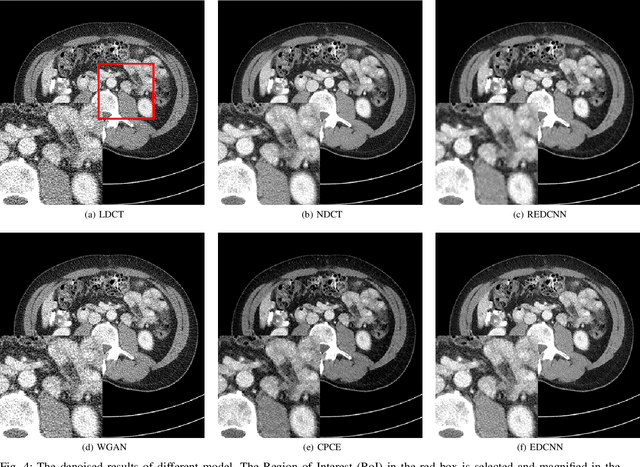

In the past few decades, to reduce the risk of X-ray in computed tomography (CT), low-dose CT image denoising has attracted extensive attention from researchers, which has become an important research issue in the field of medical images. In recent years, with the rapid development of deep learning technology, many algorithms have emerged to apply convolutional neural networks to this task, achieving promising results. However, there are still some problems such as low denoising efficiency, over-smoothed result, etc. In this paper, we propose the Edge enhancement based Densely connected Convolutional Neural Network (EDCNN). In our network, we design an edge enhancement module using the proposed novel trainable Sobel convolution. Based on this module, we construct a model with dense connections to fuse the extracted edge information and realize end-to-end image denoising. Besides, when training the model, we introduce a compound loss that combines MSE loss and multi-scales perceptual loss to solve the over-smoothed problem and attain a marked improvement in image quality after denoising. Compared with the existing low-dose CT image denoising algorithms, our proposed model has a better performance in preserving details and suppressing noise.